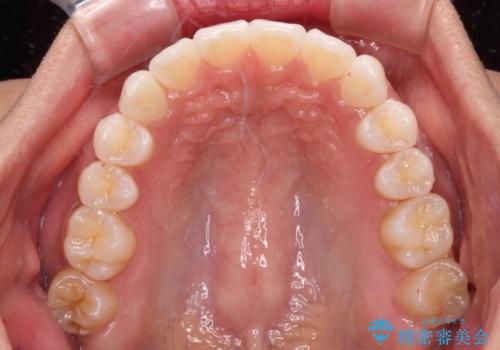

- 前に出ている上顎前歯が気になるとのことで来院された患者様です。

インビザラインを用い、IPR(歯と歯の間を削る)と歯列全体を後方に移動させることで、可能な限り前歯の突出感を改善することとしました。

元々の歯列も整っており、横顔の印象の出っ歯ではなかったため、仕上がりに満足できない可能性があると心配しておりましたが、口が閉じやすくなり、患者様には大変満足していただきました。